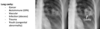

Lobar collapse on CXR

raised hemidiaphragm, tracheal deviation - may be from obstruction WITHIN airway e.g. tumour/mucous plugging/inhaled FBAO or OUTSIDE the airway e.g. tumour/lymphadenopathy

Right upper lobe collapse

Right middle lobe collapse Depression of the horizontal fissure with subtle middle zone pacification

Right lower lobe collapse Sail sign = triangular opacity with double R heart edge

Left upper lobe collapse Veil sign = whole left lung field covered by veil (extends from left hilum and fades inferiorly) with elevated left hemidiaphragm and tracheal deviation

Left lower lobe collapse Sail sign = triangular retrocardiac opacity with apparent double R heart edge